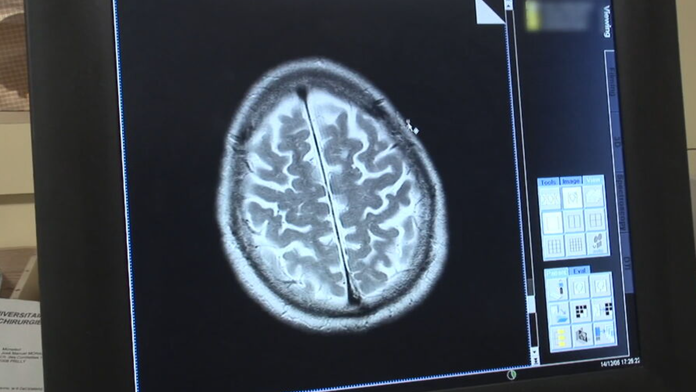

Mozog. Ilustračná snímka Zdroj: TV Markíza

Vedcom sa podarilo určiť vek, kedy mozog začína starnúť.

Prekvapivo je to skôr, ako by si mnohí mohli myslieť. Mozog starne už v strednom veku, to znamená okolo 40. roku života, uvádza nová štúdia